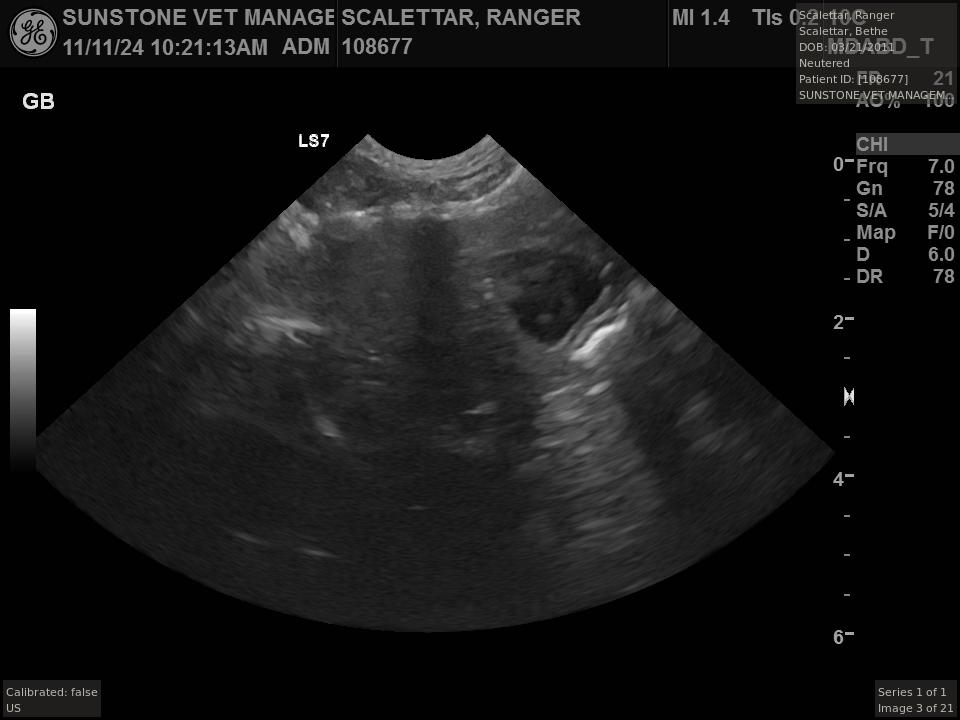

The veterinarian generated a series of images showing different organs and substructures by

changing the position and orientation of the ultrasound transducer. The images were collected

in a defined order, which is repeated from patient to patient, ensuring that nothing is missed. In

Ranger's case, the sonographer collected about twenty images during an examination that

lasted about fifteen minutes.

The sonographer stated that Ranger's ultrasound images were largely normal for an older cat. In particular, they show changes in the kidneys that are commonly noted in geriatric cats and that reflect a risk for the development of chronic kidney disease. However, the images did not show any significant abnormalities in Ranger's stomach, intestines, and associated lymph nodes. Nonetheless, the results did not rule out recurrence of Ranger's small cell lymphoma.